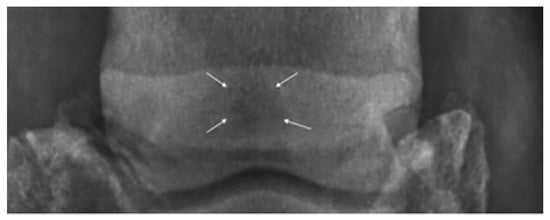

In addition, 65° DPr-PaDiO radiographs of the hooves were taken for each of the horses included in the study group, revealing enthesophytes on the medial and lateral aspects of the navicular bone in three of the horses, along with increased medullary sclerosis of the navicular bone in four horses (Figure 2), while PaPr-PaDIO radiographs revealed sclerosis of the medullar cavity in two horses and increased opacity on the flexor border of the navicular bone for three horses. The LM revealed erosions of the flexor cortex of the navicular bone for two horses. Multiple lesions were observed in the case of six horses, and in only two horses did we observe a singular lesion [20]. The radiographic images were read by a veterinarian radiologist with 7 years of experience in the equine field.

Figure 2.

Horses with palmar foot pain: DPr-PaDiO radiolucent area (sclerosis of the medullary cavity) in the navicular bone (white arrows).